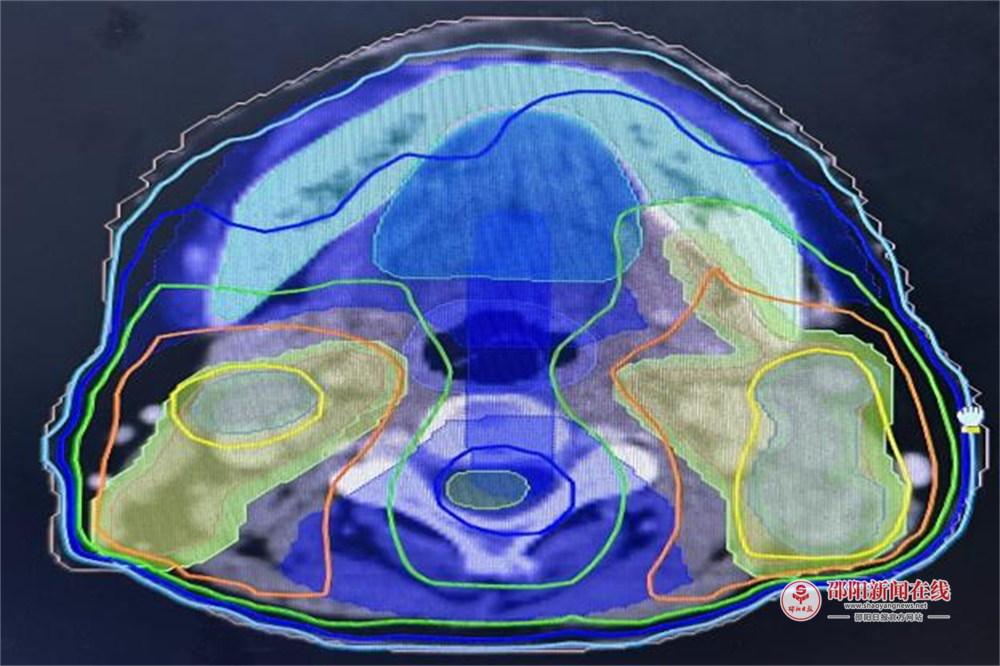

团队采用调强适形放疗(IMRT)联合同步化疗方案,邀请影像科专家共同精准勾勒鼻咽部肿瘤边界,实现 “肿瘤区域高剂量聚焦、颅底及咽旁间隙等关键部位低剂量保护”。针对鼻咽癌易侵犯周围组织的特性,医生为每位患者定制个体化靶区,使射线像 “手术刀” 般精准清除病灶,显著提升了局部控制率和生寸率。